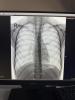

Сделали рентген в мсч 157

чистый (Есть что-то типа на бронхит похожее)

У дочки была пневмония, температура держалась 37.3-37.5, сделали рентген оказалась односторонняя, отправили домой с антибиотиками, но сказали если будет подниматься температура вызывать скорую. Ещё сказали если бы на рентгене была двусторонняя то сразу же бы положили в больницу

@voroncova11 у нас была пневмония тогда, при чем двухсторонняя. Без кашля и без высокой температуры.